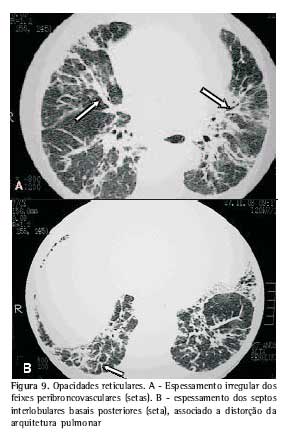

Opacidades reticulares. Resultam de uma combinação de espessamento dos septos interlobulares e do interstício intralobular. O espessamento septal localiza-se preferencialmente ao longo dos feixes peribroncovasculares, mas pode ocorrer em outras topografias (Figura 8).

Opacidades lineares irregulares foram também descritas junto aos feixes broncovasculares e atribuídas a manifestações precoces da fibrose pulmonar (Figura 9)(7,9).